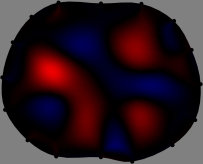

for [23]. This shows that the column vector is like an EEG (electroencephalography) data induced by dipole sources with directions at locations . Given that two dipole sources at distant locations produce mutually independent data, the correlation between and decreases with the distance between and . Fig. 2 shows a few images of the correlation as a function of for four different positions . The correlation decreases rapidly as the distance increases. In the green regions where the correlation is almost zero, is nearly orthogonal to .

Fig. 2 shows that if and are far from each other, the corresponding columns of the sensitivity matrix are nearly orthogonal. This somewhat orthogonal structure of the sensitivity matrix motivates an algebraic formula that directly computes the local ensemble average of conductivity changes at each point using the inner product between changes in the data and a scaled sensitivity vector at that point: